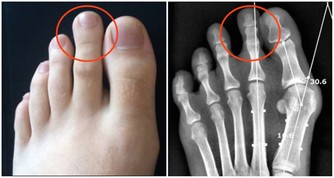

二,腰圍警戒線—— 100公分

有調查表明,腰圍每增加約11公分,患癌症的風險提高13%,臀圍每增加8公分,患腸癌風險提高15%。

北京大學腫瘤醫院胃腸腫瘤中心符濤指出,腰圍超過100公分,不只是心腦血管疾病,患結直腸癌的風險都會增加2倍以上。

腰腹部過大,脂肪堆積,會引起機體慢性炎症反應,從而增加高血壓、糖尿病、冠心病等嚴重疾病的患病風險。

記住,想要身體健康,45歲後的你,腰圍不要超過100公分,多數都是男性會超標。